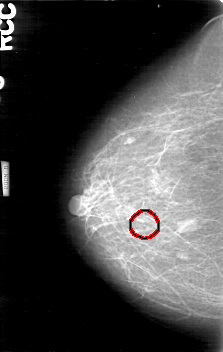

D_4170_1.RIGHT_CC

RIGHT_CC LINES 5266 PIXELS_PER_LINE 3331 BITS_PER_PIXEL 12 RESOLUTION 43.5 OVERLAY

FILE: D_4170_1.RIGHT_CC.OVERLAY

TOTAL_ABNORMALITIES 1

ABNORMALITY 1

LESION_TYPE CALCIFICATION TYPE AMORPHOUS DISTRIBUTION CLUSTERED

ASSESSMENT 0

SUBTLETY 2

PATHOLOGY BENIGN

TOTAL_OUTLINES 1

BOUNDARY